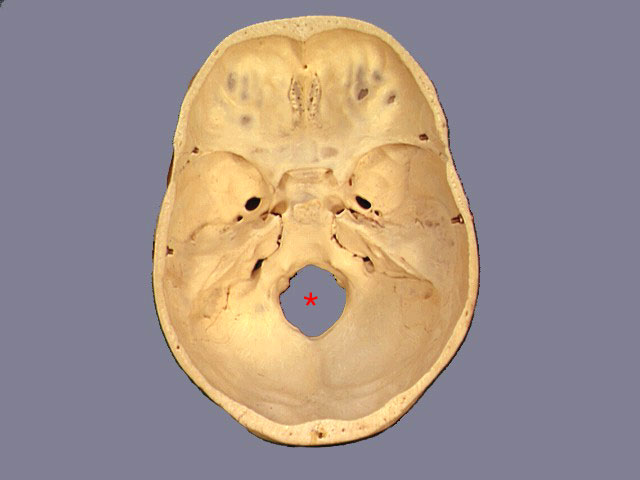

Foramen Magnum